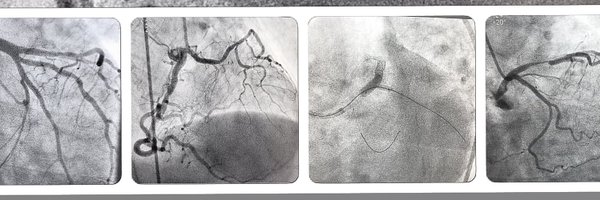

After successfull pPCI of the LAD in a 48 y/old women, as a ‘great’ introduction, I had an enormous pleausure to be an invited speaker at the #SINERGY2025 Congress, in the session Women in Cardiology, and to talk about gender specific differences in diagnosis and treatment of ACS

Is the Cx ostium still the Achilles heel of LM bifurcation PCI? Our analysis from the EBC MAIN trial is now published in @CircIntv The Cx ostium was the commonest site requiring revascularization after LM bifurcation PCI, irrespective of whether one or two stents had been

Thank you @CRT_meeting for the invitation and warm welcome in #Washington I am pleased to be a part of this great science and talking about #bifurcation #wic #CRT2025